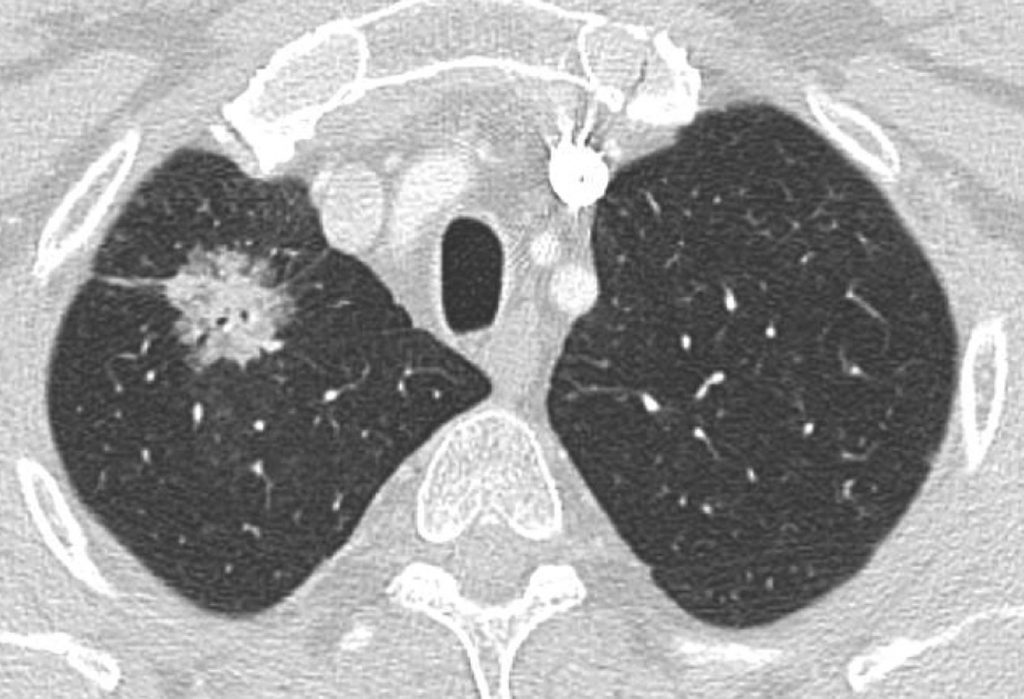

Fig. 101.2. Scanner thoracique (même patient que celui de la figure 101.1).

Macronodule du segment apical du lobe supérieur droit, de densité mixte (solide et « verre dépoli »), aux contours à la fois spiculés et lobulés. Après exérèse chirurgicale, l’examen anatomopathologique a révélé qu’il s’agissait d’un adénocarcinome bronchique.

Source : CERF, CNEBMN, 2022.